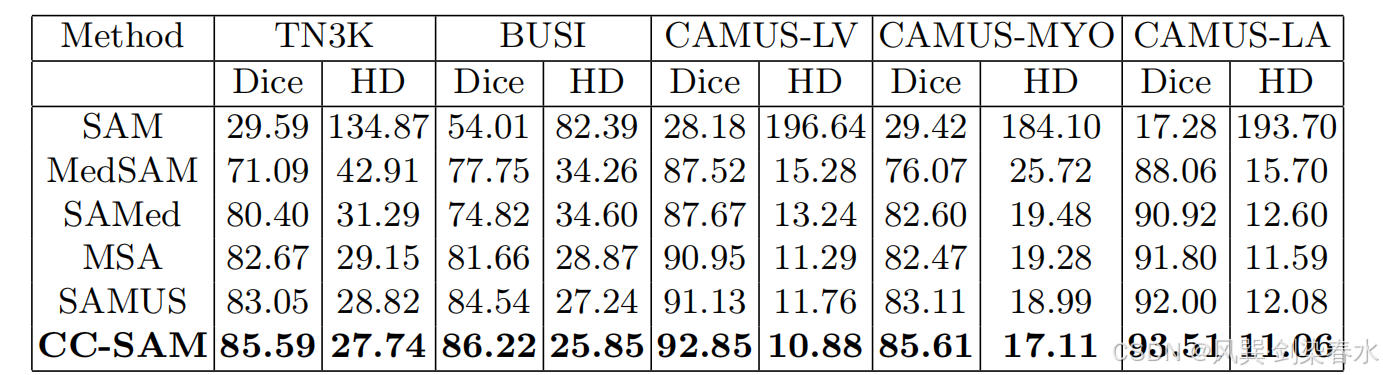

Table 2 | CC-SAM 方法与 SOTA 任务特异性技术分割甲状腺结节(TN3K)、乳腺癌(BUSI)、左心室(LV)、心肌(MYO)和左心房(LA)的定量比较:使用 Dice 评分(%)和 Hausdorff 距离(HD)来评估其表现,表现最好的结果用粗体突出显示。

Table 3 | CC-SAM 和其他基础模型在可观察的 US30K 数据上的定量比较: